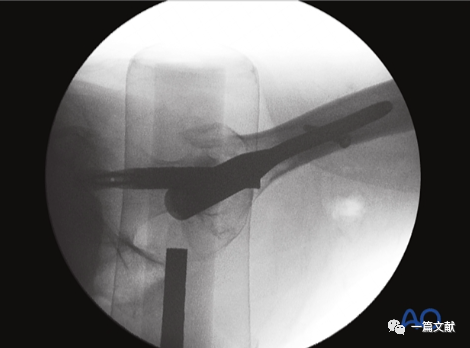

轴位片的作用:判断复位质量;观察头颈骨块与股骨干对线情况;确定导针准确的置入点。如下图:

轴位片上标准的内固定位置(中心到中心)

下图左侧正位片与右侧的轴位片,显示了内固定的良好位置(位于头颈中心与髓腔中心)。需要注意的是这些标准的术中透视图像,只有在良好骨折复位的基础上才能获得。

只有如下图右侧的轴位片图像才能判断内固定在头颈骨块中的位置(左侧为侧位片)

同一患者的侧位像与轴位像的内固定透视图像如下图: